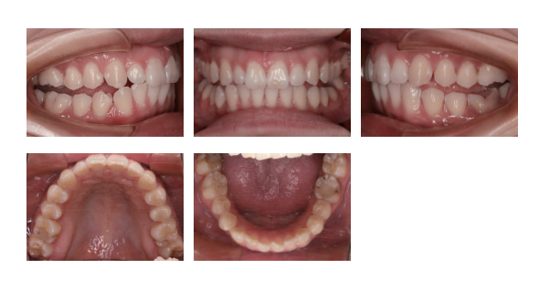

実際に、ここまで改善しています

見た目だけでなく、構造も改善しています

Before / After

横顔は、ここまで変わります

変わるのは、歯並びだけではありません

← スライダーを動かして比較

※ 個人の治療結果であり、全ての方に同様の結果を保証するものではありません。

※歯並びだけでなく、骨格バランスの改善による変化です